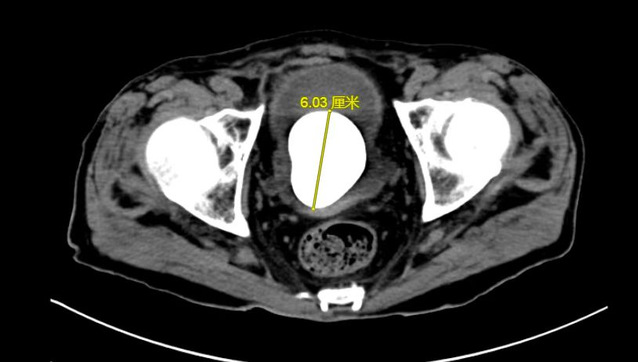

数月来,徐老伯常有尿频尿痛症状,由于近期症状明显加重,甚至出现反胃、食欲不振致使精神萎靡的情况,在当地医院就诊时,被查出膀胱内有一枚6cm*5cm大小的膀胱结石。

由于徐老伯已经84岁了,手术风险高,辗转多家医院没有得到合适的治疗方案。家属推着轮椅上的徐老伯来到了金沙娱乐城app 泌尿外科门诊上,主任医师陈建春仔细询问病史及阅片后,第一时间将患者收入病房。经过详尽的检查,陈建春团队发现患者精神萎靡部分原因是由于患者营养状态差导致,联合营养科为患者制定了提高营养状态的治疗方案。

目前,治疗膀胱结石的主流手段为经尿道钬激光碎石术,但考虑到患者高龄,且营养状态虽较前好转,但仍较正常老年患者不足,若采取经尿道手术治疗患者“鹅蛋”大小的膀胱结石,患者难以耐受3小时甚至更长时间的手术及麻醉过程,因此,在与患者沟通后,陈建春团队选择了传统的膀胱切开取石术。最终,在手术麻醉、ICU及护理团队的共同协作下,陈建春主任团队顺利将“鹅蛋”大小的膀胱结石自患者体内取出,整个手术过程仅用30分钟。